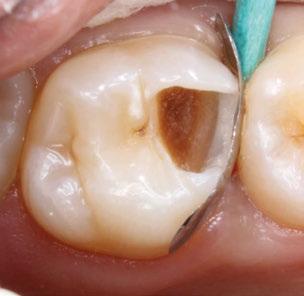

Exploración Intraoral

Presenta un estado oral deficitario. Parcialmente edéntula, con colapso de mordida, migración dental patológica, restauraciones de resina antiguas fisuradas y filtradas, transparencia y exposición de cámara pulpar secundaria a desgastes con pérdida de estructura e integridad de tejido dental importante (Figuras 1 a 4). Portadora a tiempo parcial de prótesis removibles desadaptadas de más de 10 años de antigüedad, refiriendo incapacidad de adaptación a este tipo de prótesis.

Exploración radiológica

Mediante CBCT constatamos atrofias óseas severas y disminución de soporte óseo periodontal en relación con las piezas dentales.

Figura 3. Visión intraoral oclusal mandibular. Figura 4. Visión intraoral frontal. Figura 1. Visión intraoral oclusal maxilar. Figura 2. Visión lateral izquierda intraoral. Figura 7. Escaneado intraoral maxilar con Dexis IS3700. Figura 8. Escaneado intraoral mandibular con Dexis IS3700. Figura 5. Visión extraoral lateral sonrisa.